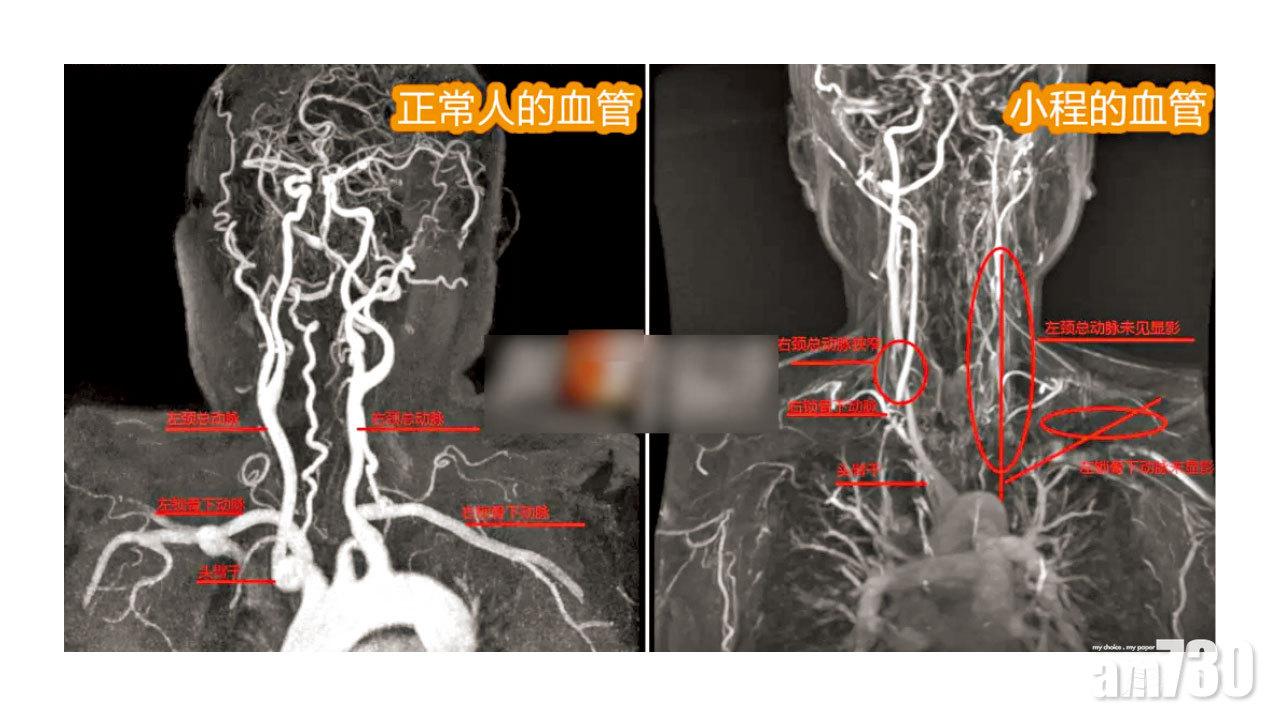

深圳一名24歲女子小程(圖)上月中突然暈倒送院,醫生初時診斷為「中風」,未料深入檢查後卻發現,小程的血管狹窄、閉塞得有如70歲老人,但其本人卻無吸煙或喝酒等引致相關症狀的高危習慣,最終醫生綜合其平日不時頭暈、四肢乏力等症狀,推斷其患上「主動脈弓綜合症」,即俗稱的「東方美女病」,而且相信是其時常思念「玩失蹤」的異地戀男友,加上工作及為男友還貸款的壓力而誘發。

此外,小程近半年常因思念男友而失眠,而且記憶力下降、雙腿經常突然發軟及不時頭暈等,上月18日晚加班回到宿舍洗澡後,更突因頭暈倒地,無法說話、半身不能動彈兼有點意識不清,最後爬出去向室友求救,約半小時後被送至深圳市第三人民醫院。醫生指,幸準確識別到小程患「東方美女病」並對症下藥,否則會延誤治療,導致其半身不遂。醫生又指,東方美女病主要見於30歲以下亞洲女性,發病原因未明,症狀多為頭暈及四肢乏力,但病人往往以為只是疲倦,直至急性發作才重視。